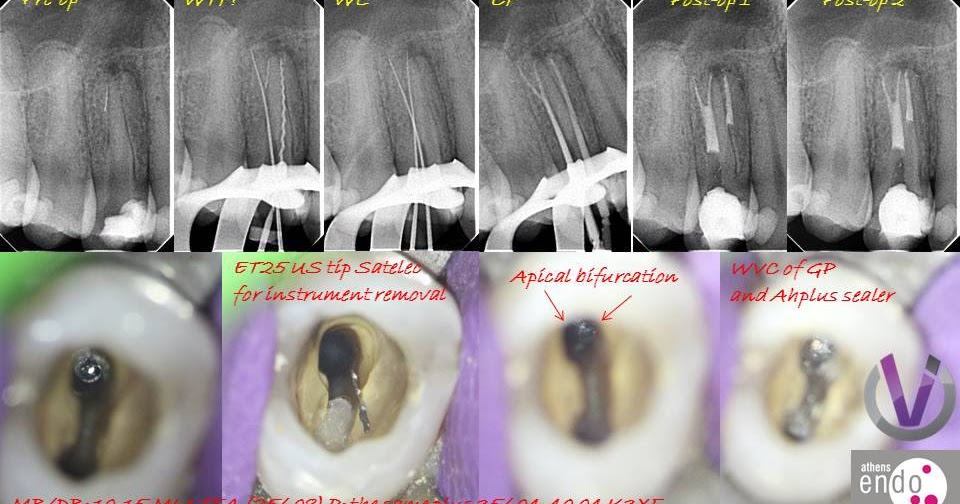

The tricky lower first premolar with 4 canals - Style Italiano Endodontics